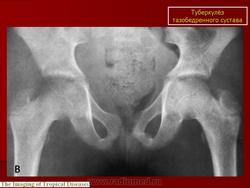

При рентгенологическом исследовании в преартритической фазе самым ранним симптомом является остеопороз, который может быть незначительным и выявляться лишь на сравнительных рентгенограммах с захватом двух тазобедренных суставов. Еще до появления туберкулезного остита могут отмечаться изменения со стороны мягких тканей в виде увеличения теней межмышечных прослоек между контурами суставной сумки и малой и средней ягодичными мышцами (симптом Ланге - Будинова). Отмечается также асимметрия костей малого таза (симптом Пинхасика), обусловленная неправильным положением больного из-за атрофии мышц, или наоборот утолщением сустава на больной стороне, или вследствие болевой контрактуры. Зная наиболее частую локализацию туберкулезных оститов вокруг тазобедренного сустава можно выявить участки нарушения костной структуры, нечеткость костных трабекул. Спустя 1,5-2 месяца выявляются очаги деструкции костной ткани с нечеткими неровными контурами, которые могут содержать множественные губчатые секвестры. Наиболее часто туберкулезные оститы располагаются в костях, образующих вертлужную впадину, реже они встречаются в шейке, и как исключение в головке бедренной кости. Причем очаги деструкции костной ткани, расположенные в вертлужной впадине, лучше выявляются на задних рентгенограммах, а очаги деструкции в шейке бедра, особенно в нижне-внутреннем отделе ее лучше выявляется на рентгенограммах с отведением бедра (по Лауенштейну). У некоторых больных наблюдается ранняя деформация ядра окостенения головки бедра в виде его увеличения.

Артритическая фаза (при переходе процесса на сустав) на рентгенограммах характеризуется усилением остеопороза, который постепенно распространяется на все кости нижней конечности. Суставная щель асимметрично суживается, больше в верхне-наружных отделах. В дальнейшем сужение суставной щели достигает значительной степени. Суставные поверхности костей теряют свои очертания, их контуры становятся нечеткими, неровными. Выявляются краевые, без четких контуров содержащие секвестры, очаги деструкции костной ткани. Последние могут вызывать значительные разрушения вертлужной впадины, головки и даже шейки бедренной кости, смещение головки бедра вверх.